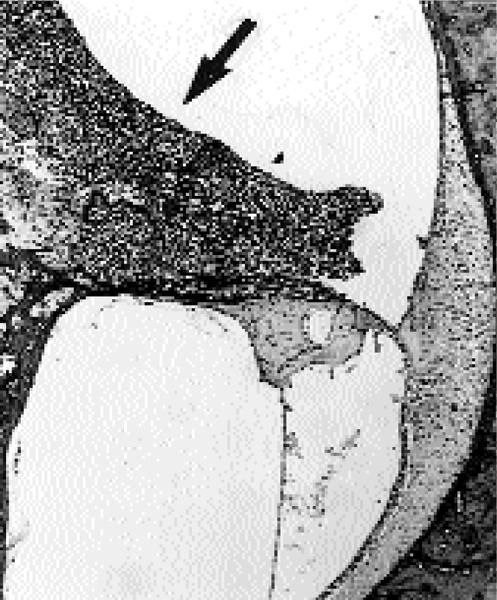

Experimental infection of conventional pigs with Streptococcus suis serotype 2 by aerosolic exposure.

Acta Vet Scand. 2001;42(2):303-6. doi: 10.1186/1751-0147-42-303.